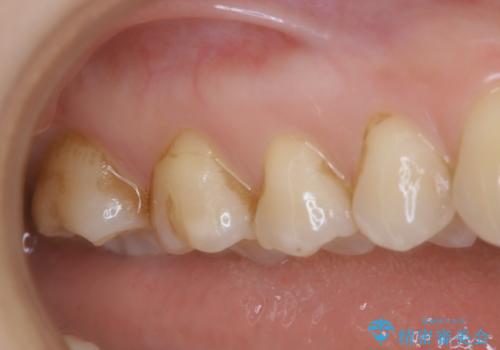

治療中の仮歯もPMTCで白くきれいに